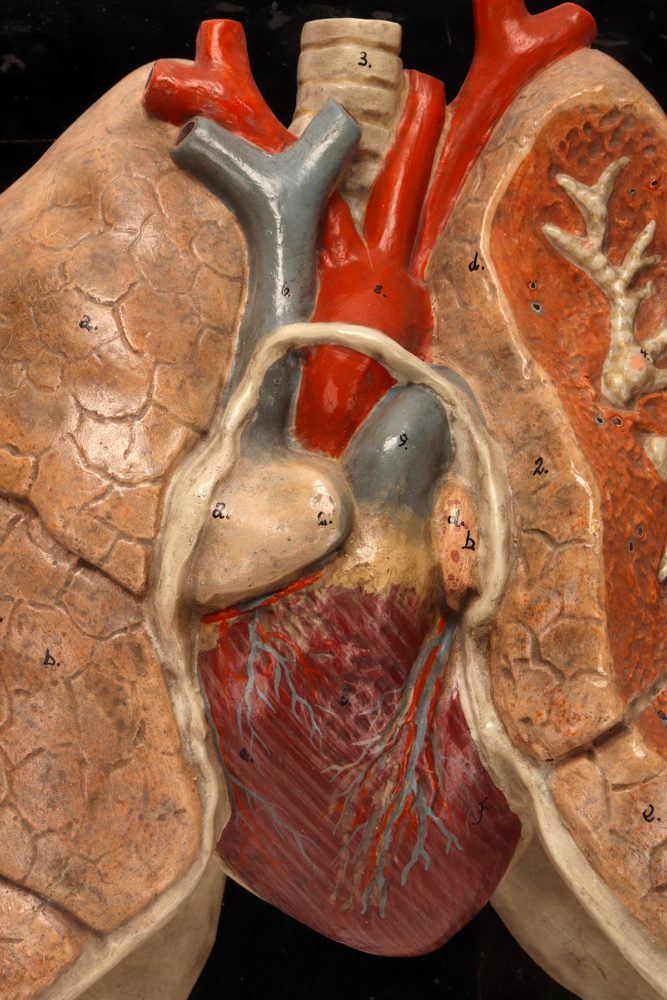

Anatomical model for class of the lungs and heart, Germany 1920.

Rare anatomical model for class, depicting human lungs and heart, made out of painted plaster, mounted on a black fruit wooden base. By Louis M. Meusel, Germany circa 1920.